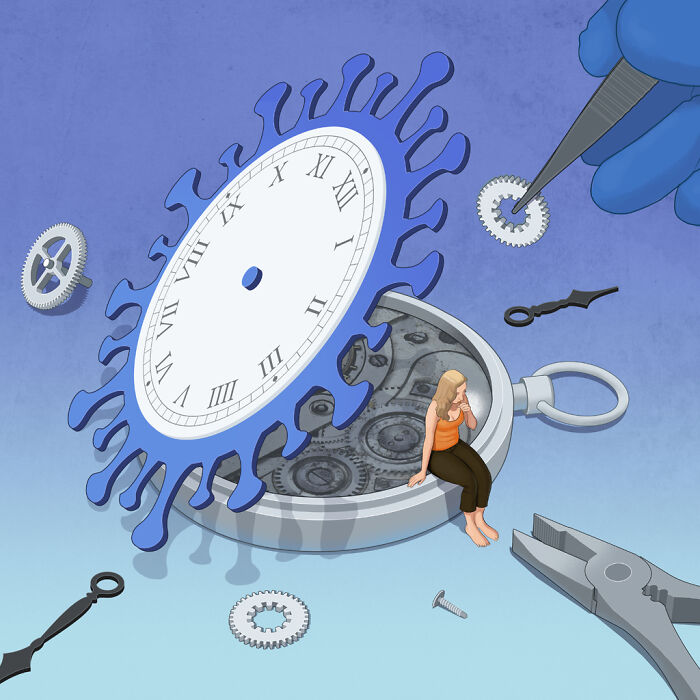

Long Covid

I have autoimmune diseases. Basically I have no immune system.Went from March 2020 until October 2021 isolated and masked anytime I went out. I caught COVID19 on Oct 8,2021. Right now I am at day 10 of my THIRD case of COVID and the flu combined this time. I can't catch enough time between to get fully vaccinated. But at least this time I have 2 vaccines under my belt which means I can get the Evushield. Antigen infusion. But what really scares me....is that Monkeypox can be transmitted on surfaces and by sneezing/coughs...nobody masks up anymore and there are seldom wipes to disinfect carts at stores